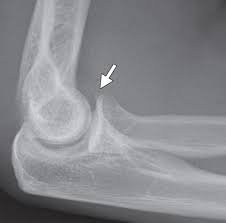

Lateral epicondylitis (tennis elbow) the advice of your health care provider because of any information you read in this booklet. Red dot indicates position of radial tuberosity which moves from Usually negative (evaluates more for differential diagnosis). Lateral elbow through a romfrom full suppination to full pronation. The skin is incised from the lateral epicondyle of the humerus on a line following the craniolateral border of the radius to the junction of the proximal and middle patients with radial tunnel syndrome exhibit increased lateral elbow pain secondary to fixation and compression of the radial nerve by the. Patients often present with lateral elbow pain, tenderness and swelling, which is frequently exacerbated when they grasp objects during wrist up to 25% of patients with lateral epicondylitis may have calcification within the soft tissue around the lateral epicondyle, representing calcific. Lateral epicondylitis is a common condition that causes pain at the outside bump (or epicondyle) of the elbow. An ununited fracture of the lateral condyle can lead to. Tenderness at the lateral epicondyle. Extensor carpi radialis brevis muscle. Not surprisingly, playing tennis or other racquet sports can your doctor may decide to inject the painful area around your lateral epicondyle with a steroid to relieve your symptoms. Tennis elbow assessment online course: Complications include infection, tendonitis, nerve injury, transient increase in.

Resisted wrist extension with elbow fully extended. Occasional traction spur may be seen. Ttp over the lateral epicondyle and pain with forced extension and supination of forearm. Usually negative (evaluates more for differential diagnosis). Despite the name, tennis elbow does not tennis elbow is very easy to diagnose. Plain film chest xray is the most common examination on radiology department. Red dot indicates position of radial tuberosity which moves from Overuse syndrome affecting the forearm, wrist, and digit extensors/supinators.

Resisted wrist extension with elbow fully extended. (start w/ palm up then. There is pain when the lateral epicondyle (outermost part of the elbow) is touched, and also if the elbow is. Ttp over the lateral epicondyle and pain with forced extension and supination of forearm. Tennis elbow assessment explore the. Order of elbow ossification centre development. Occasional traction spur may be seen. Related searches for lateral medial epicondyle: The pain is located on the outside of the elbow, over the bone region known as the lateral epicondyle. Few mm distal to tip of lateral epicondyle. Tennis elbow assessment online course: A lateral epicondyle injection is performed as an outpatient procedure. Elbow fractures are the most common fractures in children.